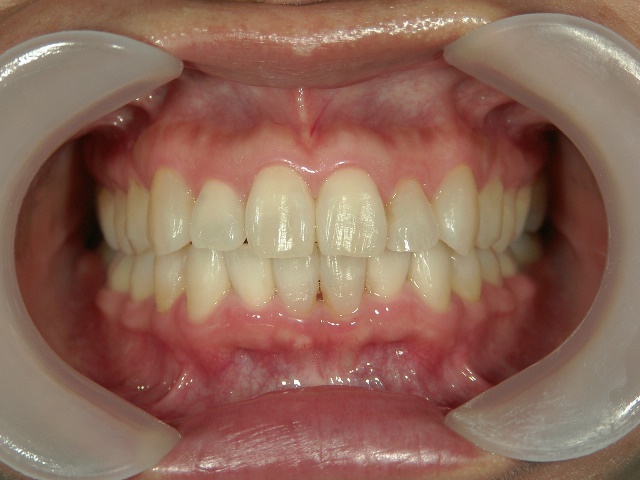

矯正歯科 治療後矯正歯科 プチワイヤー矯正 治療後矯正歯科(プチワイヤー矯正)治療後

矯正歯科 治療後 ミニインプラントを2本埋入し、下顎前歯を圧下